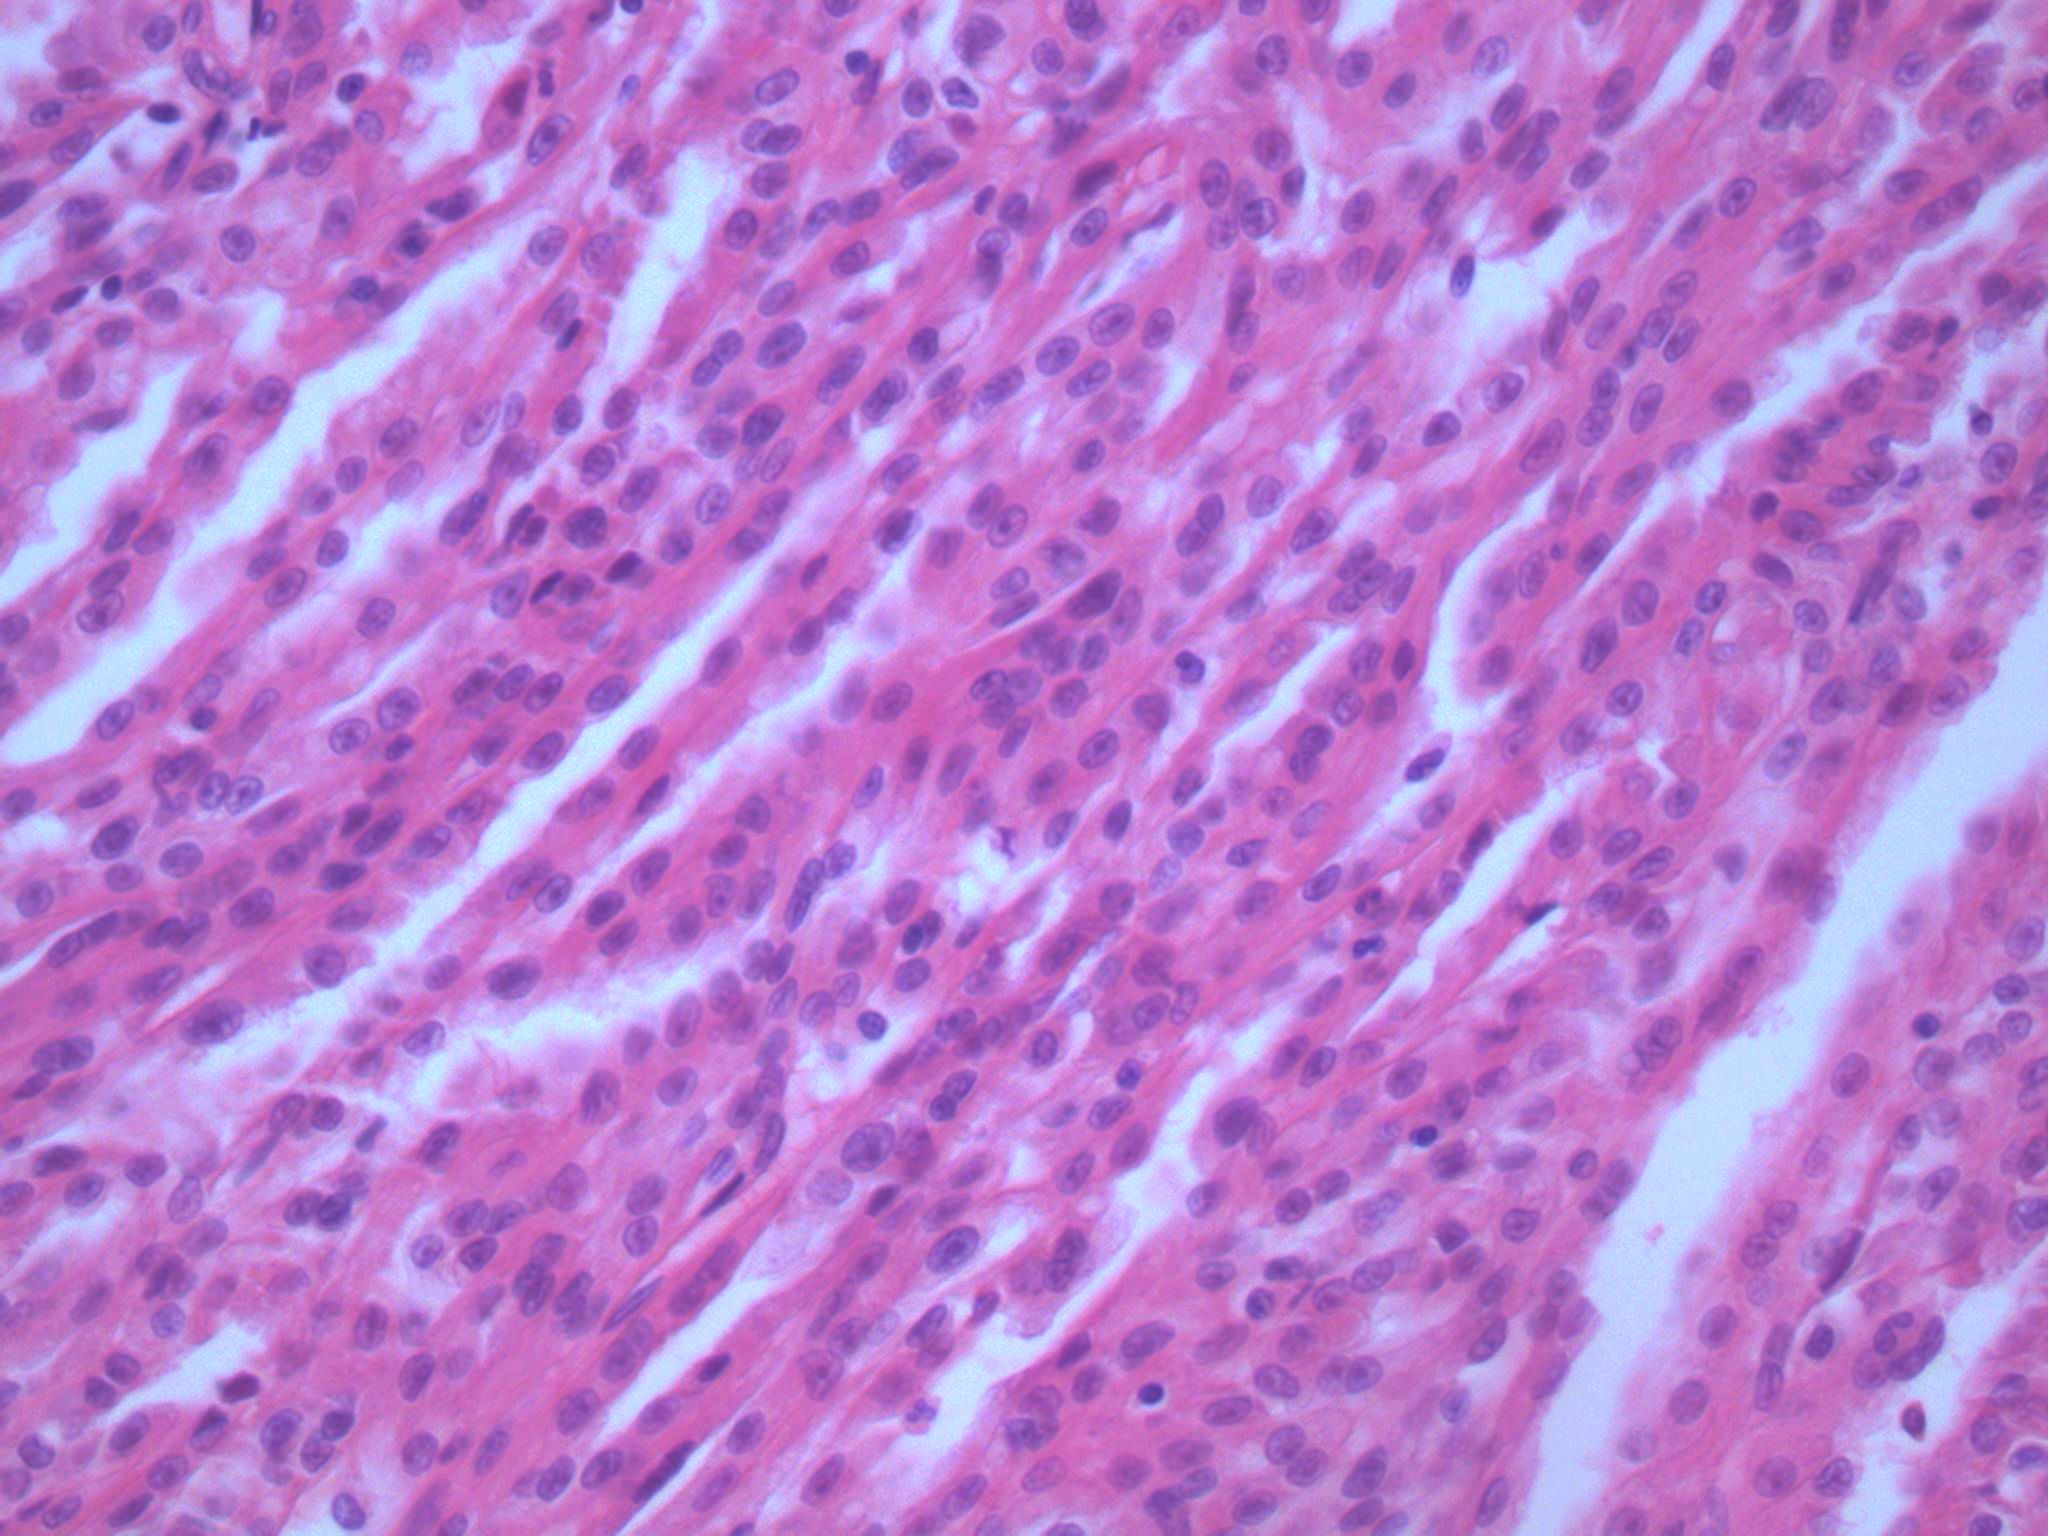

Consensus grade: Mucinous tubular and spindle cell carcinoma

Tumour composed of elongated clefts and tubules